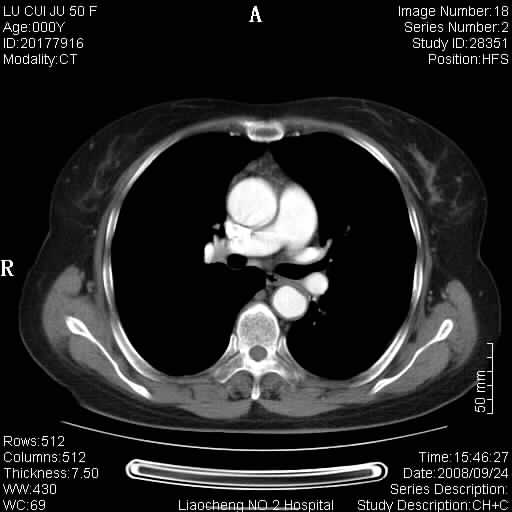

标题: CT15870:F50Y,纵膈占位,是不是胸腺瘤,请各位高手讨论。

临床表现为重症肌无力;ct增强扫描可见前纵膈胸腺部位弥漫性簇状软组织节结灶,不知道是不是胸腺瘤,请各位高手讨论。

胸腺外缘稍向外突,未见确切占位改变。结合临床考虑胸腺增生可能性大。